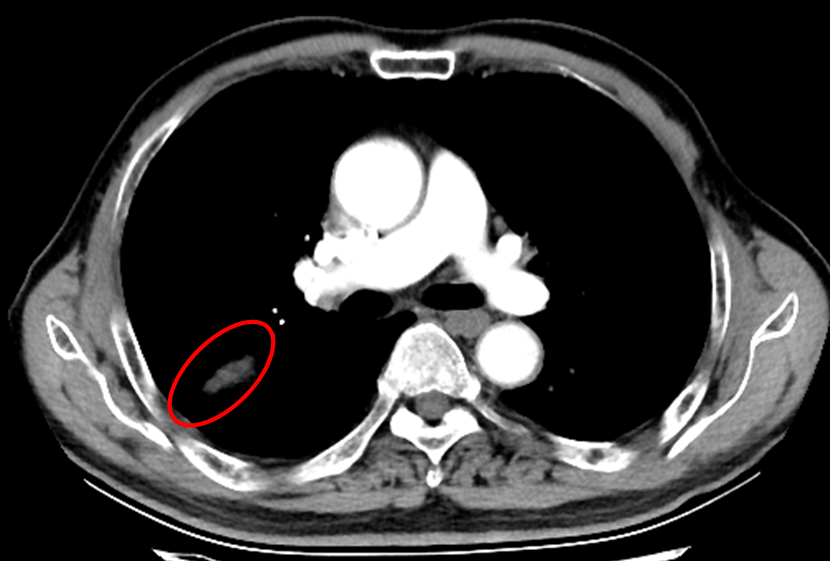

最终老唐肺结节的穿刺病理结果为肺腺癌,至今已随访4年多了,腺癌结节灭活后成了瘢痕纤维灶。

△胸部增强CT提示右肺无强化残存瘢痕灶